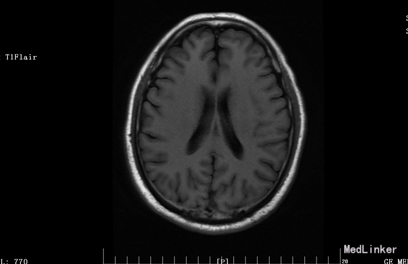

入院体检:T 36.9°C,P 87次/分,R 22次/分,BP 136/69mmHg。全身皮肤无黄染及出血点,全身浅表淋巴结未扪及肿大。双肺呼吸音清,未闻及干湿性罗音。心率87bpm,律齐,各瓣膜听诊区未闻及杂音。腹平,腹肌软,肝脾肋下未及,无压痛、反跳痛,肠鸣音正常。脊柱四肢无畸形,双下肢无水肿。神经系统:神清语晰,对答切题,记忆力、定向力、计算力正常,查体合作。双侧瞳孔等圆等大,直径约3mm,对光反射灵敏,双眼球活动自如,未见眼震。双侧额纹对称,双侧鼻唇沟对称,伸舌居中。四肢肌张力正常,左侧肢体肌力II级,指鼻试验、跟膝胫试验、闭目难立征未能配合检查。双侧腱反射对称存在,双侧巴氏征未引出。颈软,双侧克氏征、布氏征(-)。 辅助检查:生化:超敏C反应蛋白:2.6mg /l、乳酸脱氢酶(LDH):105U/L、甘油三酯(TG):2.32mmol/L、尿酸(URIC):416umol/L;同型半胱氨酸:14.3umol /l;D-二聚体定量:270ng /ml;糖化血红蛋白(HbA1c):5.1%;红细胞沉降率:3mm/h;人脂蛋白相关磷脂酶A2:378ng /ml;风湿十二项:(-); 胸部DR:主动脉硬化,双肺未见异常。心脏彩超:LVEF:66%。心内结构未见异常。 心内未见异常血流。 左室舒张功能降低。颈血管彩超:双侧颈总动脉、颈内动脉、颈外动脉、椎动脉未见异常。 双侧颈动脉、椎动脉血流速度正常。 急诊CT未见明显异常。 头颅MR:1、 双侧额叶软化灶,病灶周边少许胶质增生;2、MRA示未见明显异常。 头颅CTA:双侧颈内动脉虹吸段、双侧大脑中动脉、双侧大脑前动脉及其分支管壁尚规则,管腔通畅未见明显狭窄;右侧椎动脉颅内段管腔较左侧稍细小,余椎动脉、基底动脉及双侧大脑后动脉管腔未见明显变窄。大脑willis动脉环清晰显示,未见明显异常。 头颅CTV:大脑静脉系统上矢状窦、窦汇、横窦、乙状窦、直窦、大脑大静脉和颈内静脉管壁规则,管腔通畅未见狭窄、畸形等异常。 动态心电图示:1.窦性心动过缓;2.偶发室性早搏;3.偶发房性早搏;4.提示不完全性右束支阻滞;5.T波改变(心率快时);6.心率变异性:正常。 脑电图无异常。

患者入院时血压不高,溶栓后立即行头颅MR,未见明显病灶。但患者体征尚存在,考虑可行头颅的薄层扫描或者改变B值。另外关于栓子的来源还有疑惑,颈动脉超声没看到动脉硬化、板块,TCD结果也正常。后来再回顾病史,患者发病的过程中有感到心慌,急诊生化血钾稍低,动态心电图报有窦性心动过缓、不完全性右束支阻滞,可考虑为心源性。另患者入院时出现左手抖动、头痛症状,为刺激性症状,但MR、CTA、CTV、脑电图未见异常。也是一个疑惑的地方,希望大家给予交流指正。患者一周后出院,左侧肢体肌力几乎恢复正常。